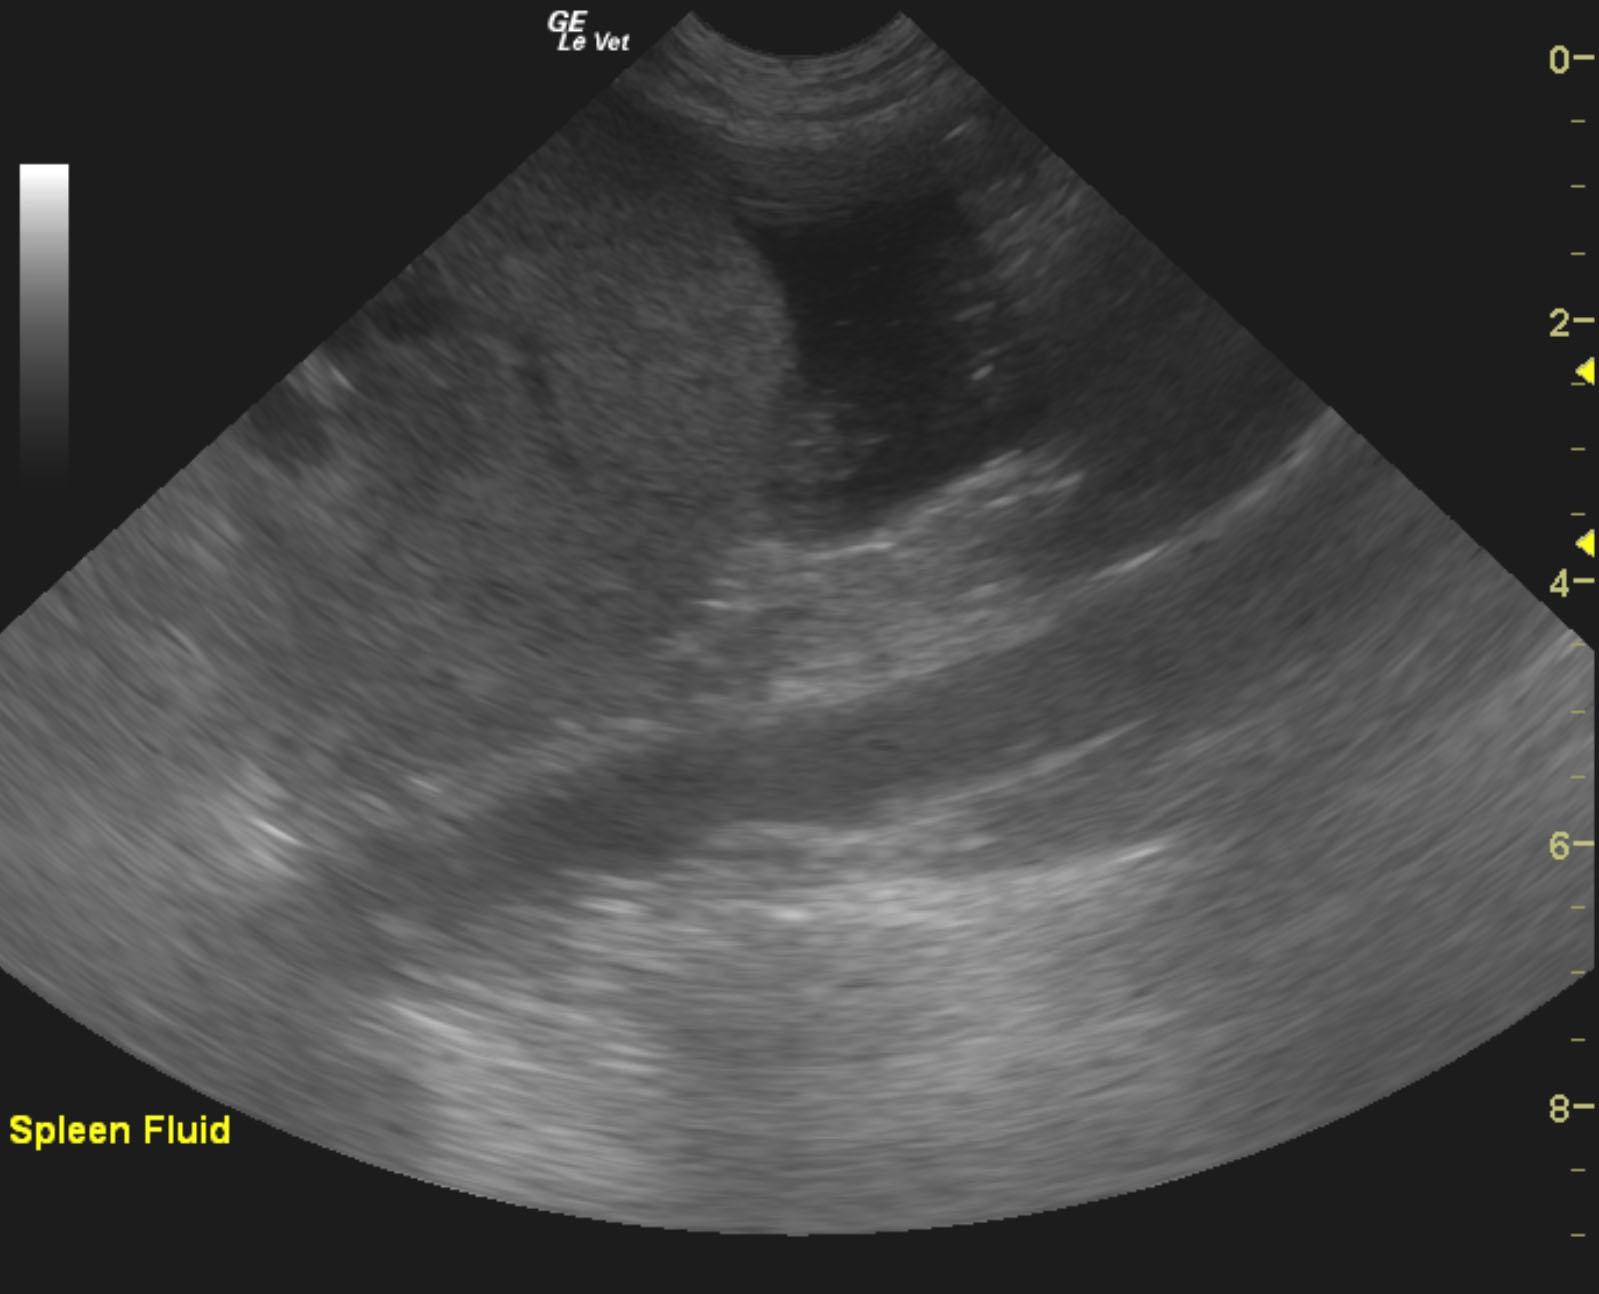

The pancreas revealed an extensive 9.7 x 7.5 cm, mixed, hypoechoic mass. The liver and spleen were riddled with multiple hypoechoic expansive nodular masses. Free fluid was noted adjacent to the spleen, which is mildly swollen. The gallbladder was unremarkable. There was also regional lymphadenopathy, with enlarged hepatic, iliac and aortic lymph nodes. Regional inflammation was noted throughout the cranial abdomen.